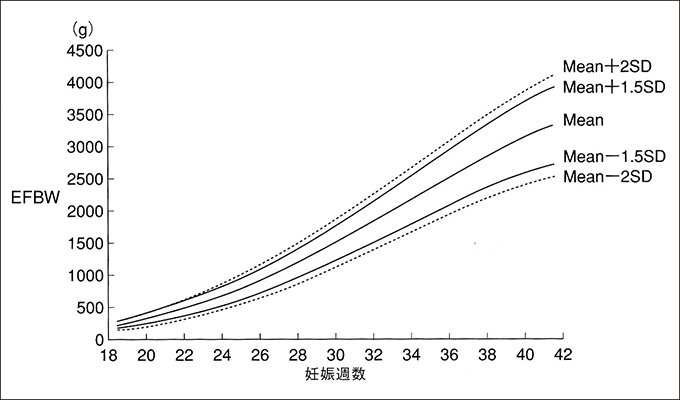

医師監修 胎児の発育曲線 成長曲線 とは?どのように見ればいいの?ゼクシィBaby。

胎児発育曲線』とは?週ごとの発育の目安を助産師が解説◎ - 株式会社エバーセンス。

胎児発育曲線』とは?週ごとの発育の目安を助産師が解説◎ - 株式会社エバーセンス。

胎児発育曲線の±2.0SDの意味は?エコー写真に学ぶ統計学 - 日常を少し掘り下げてみる。

医師監修 おなかの赤ちゃんの発育は順調? 「胎児発育曲線」とはトモニテ。

胎児発育曲線の±2.0SDの意味は?エコー写真に学ぶ統計学 - 日常を少し掘り下げてみる。